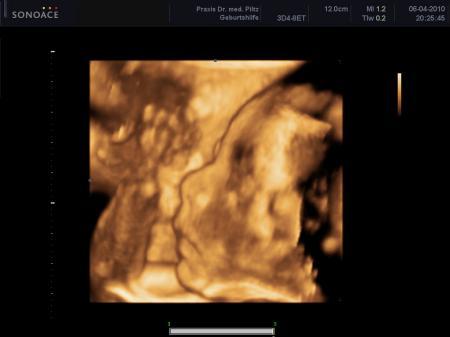

Hätte ich fast vergessen- der kleine Mann hat tatsächlich mal sein Gesicht zeigen wollen!

...falsches Foto erwischt, dies ist schon 2 Monate alt....!